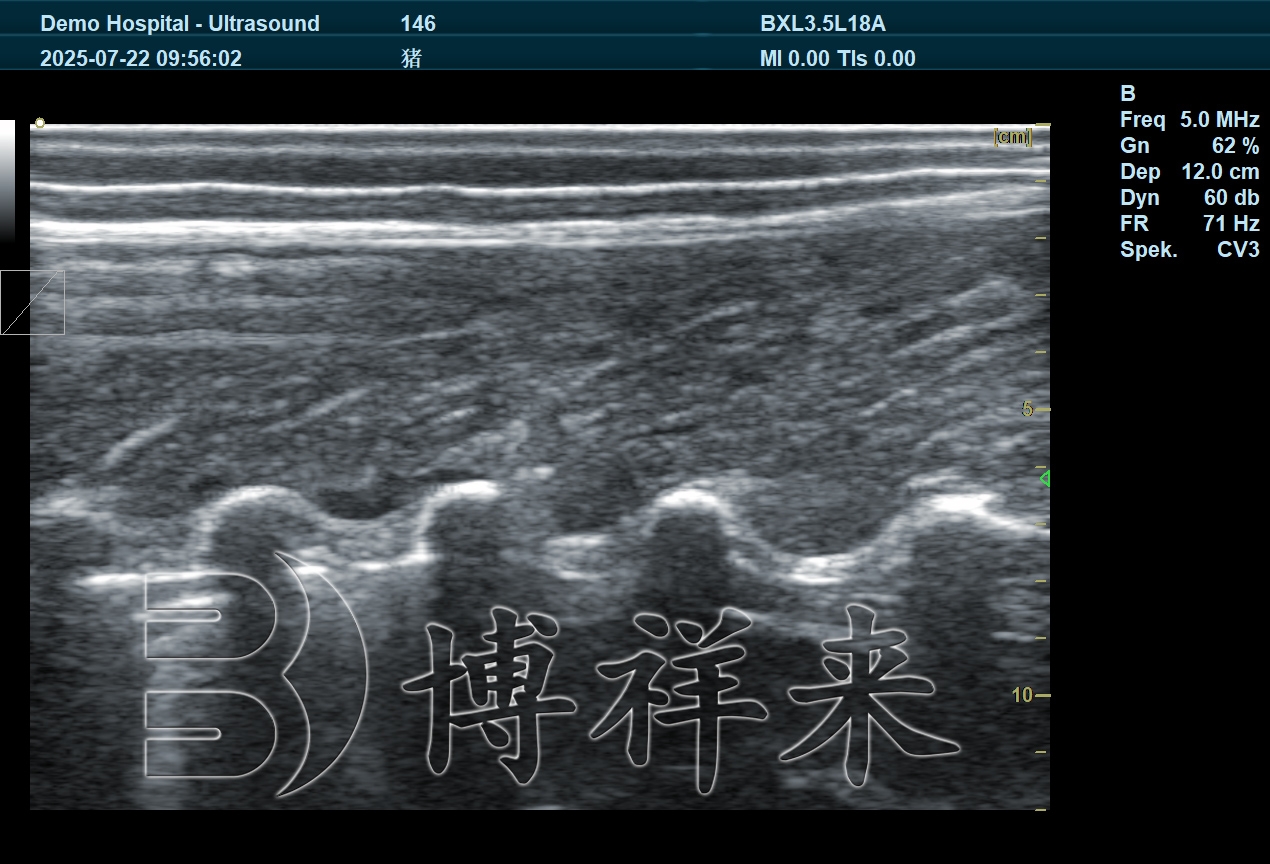

猪背膘仪通常基于兽用超声成像原理,通过专用探头获取背部脂肪层与肌肉层的回声信息,从而准确测量背膘厚度。相较于人工触摸或目测评估,猪背膘仪能够清晰区分皮肤、脂肪和肌肉结构,使测量结果更加客观、可重复。

在技术应用层面,猪背膘仪具有操作直观、测量速度快、数据稳定性强等特点,特别适合在规模化猪场中进行批量检测,为繁殖管理提供可靠的数据支持。